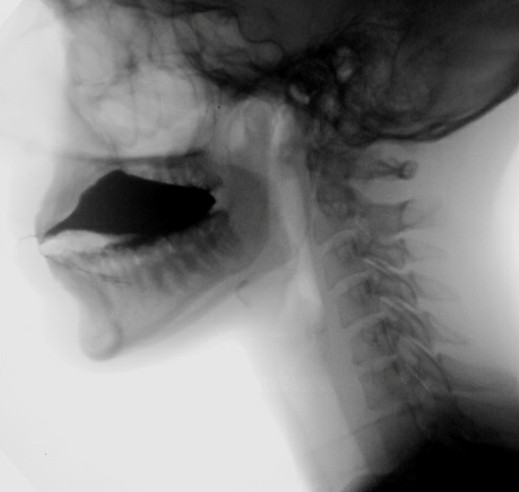

The triggering of the swallow reflex marks the beginning of the involuntary stage of deglutition and is radiologically defined by the brisk anterior-superior movement of the hyoid bone. Traditionally, this reflex has been thought to be invariably triggered when the boluses pass the radiological level of the angle of the mandible, but this depends on the consistency of the boluses being tested13,27. To standardize the assessment and avoid overcalling reflex delays, we evaluate the triggering of the reflex based on the passage of thin liquid boluses beyond the level of the mandibular angle. (Fig. 8)

Figure 8: Oropharyngeal transport of a liquid bolus. When the contrast reaches the level of the angle of the mandible, the hyoid displays a brisk anterior-superior movement in (B) signalling the start of the swallow reflex